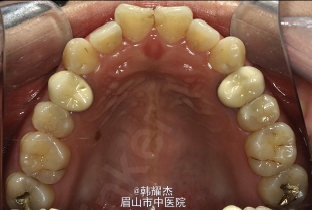

主诉:面部不对称。 病史:女,26岁,青春期时发现面部不对称,后进行性加重

面部不对称,颏部左偏,凹面型,骨性III类,高角,牙列拥挤 全景片显示右侧下颌升支明显变长,左右髁突不对称

诊断:面部偏斜、右侧髁突增生、牙列拥挤 治疗目标:纠正面部不对称,同时阻止髁突进一步增生,建立协调平衡的咬合,改善面部美观 处理:右侧增生髁突高位切断术,术后正畸治疗,根据治疗中情况看是否需要正合外科的辅助。 此病例后期未经正合外科治疗,仅通过种植钉实现了右侧后牙的压低,改正面部偏斜,治疗后面部偏斜改善效果好,患者满意。